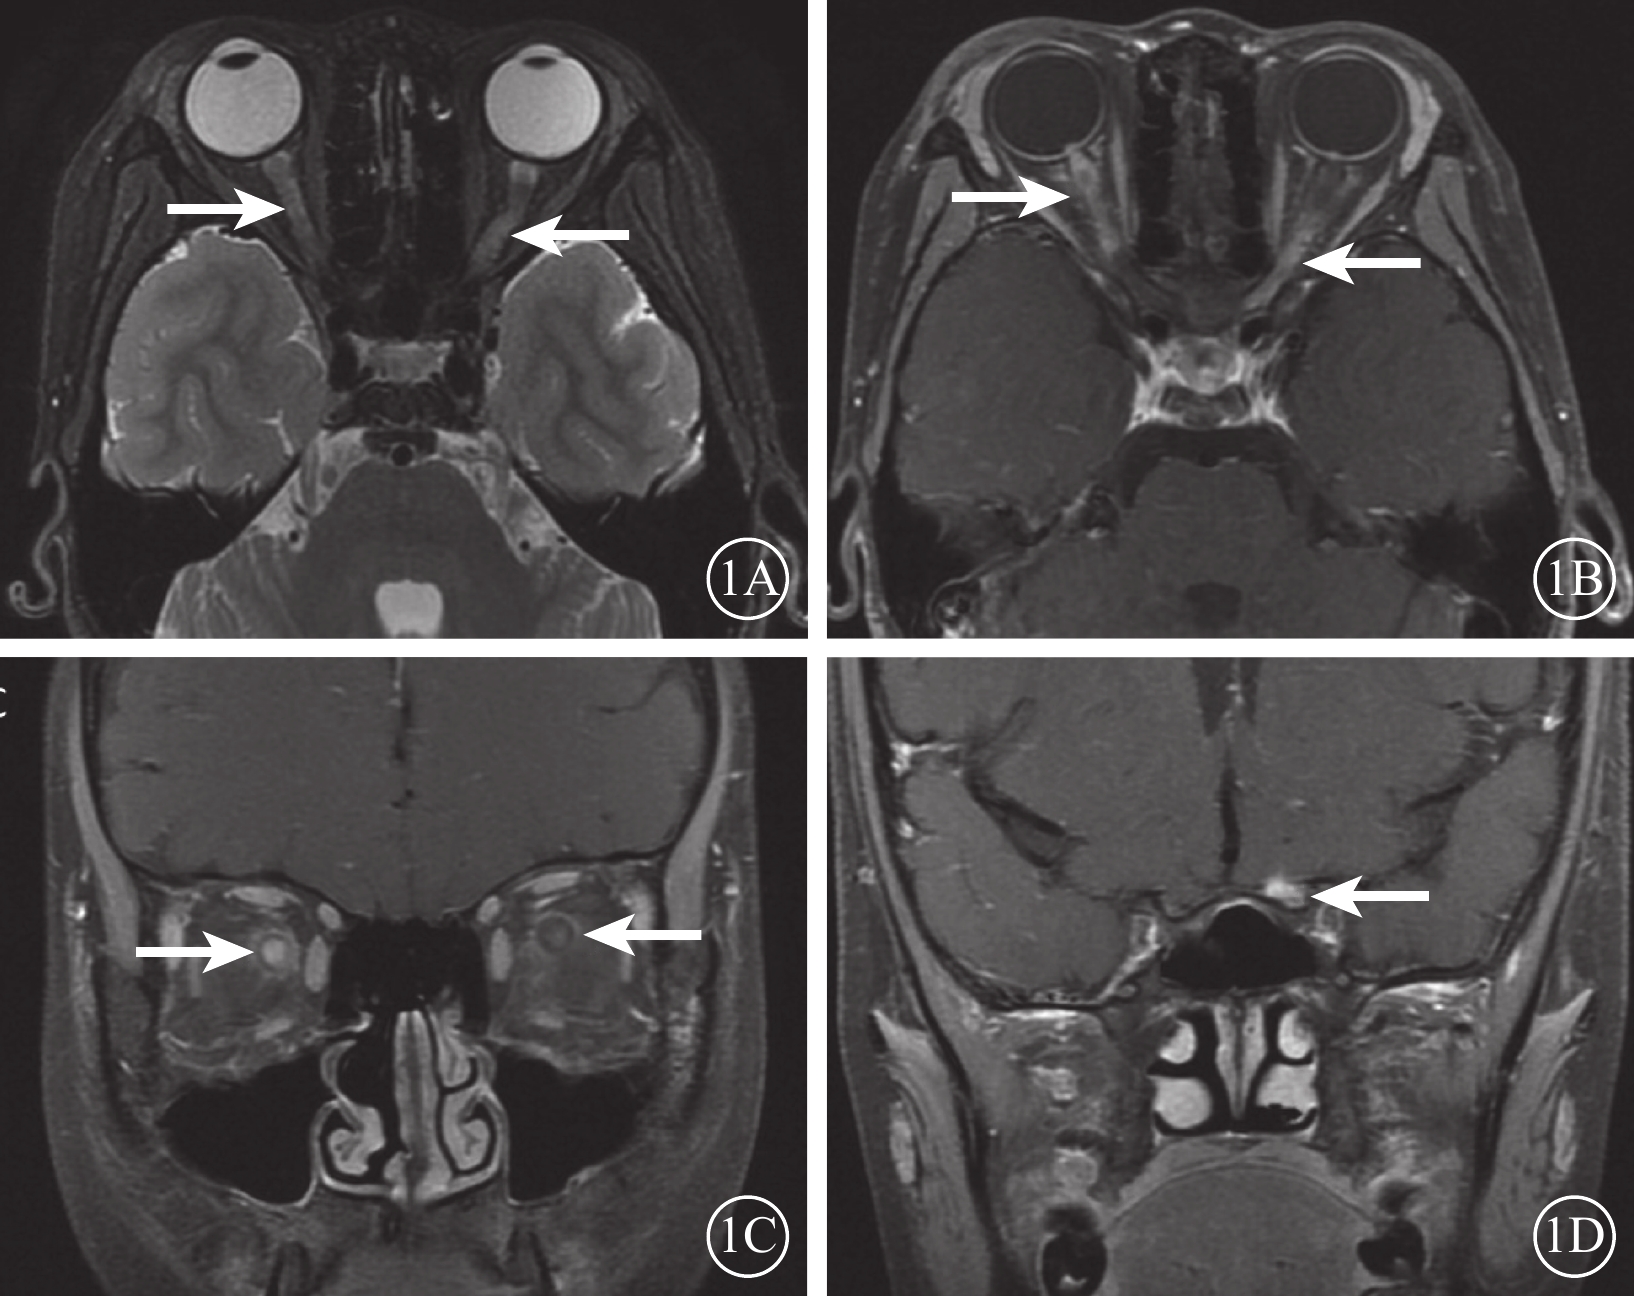

眼眶MRI檢查結果顯示,所有患兒視神經呈長T2信號。其中,伴T1釓增強掃描強化病灶(圖1)11例(78.6%)。并發脊髓炎的5例患兒,脊髓MRI檢查可見大于3個脊髓節段的病灶,呈長T2信號(圖2)。既往有癲癇病史的1例患兒,顱腦MRI檢查可見雙側腦室旁白質多發片狀長T2信號伴T1強化。

圖1

AQP4-PON患兒眼眶MRI像。1A示軸位T2加權成像,雙眼視神經眶內段、左眼管內段可見長T2信號(白箭);1B示軸位釓增強T1成像,雙眼視盤、視神經眶內段、左眼管內段可見強化,同時可見視神經周圍強化(白箭);1C示冠狀位釓增強T1成像,雙眼視神經眶內段強化伴視神經周圍強化,右側更明顯(白箭);1D示眶冠狀位釓增強T1成像,左側視神經管內段可見強化信號(白箭)